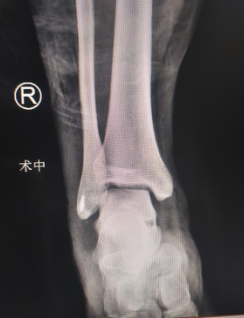

完善的术前准确后,徐明亮主任、周祥国医生手术组为患者进行了关节镜下右踝骨折复位内固定、韧带修复踝关节稳定术。通过在踝关节前侧取0.5cm的两个小切口,放置关节镜通道,在镜下复位固定骨折块,对损伤断裂的韧带进行重建修复。

术中